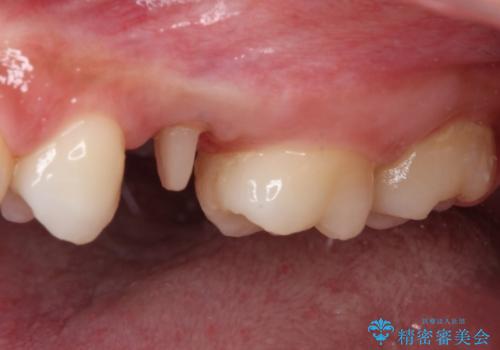

まずは虫歯を除去した上で根管治療を行い、部分矯正により骨内深い位置にまで及んだ健全な部分を引っ張り出すこととしました。

その後骨形成処置を行い、治癒を待って補綴治療を行うこととしました。

かなり深い位置にまで虫歯が及んでいたため、かなりの量を引っ張り出す必要があり、残された歯根は短く小さい状態となりました。

今後も定期的にレントゲンを撮るなど、経過を追っていく必要があります。